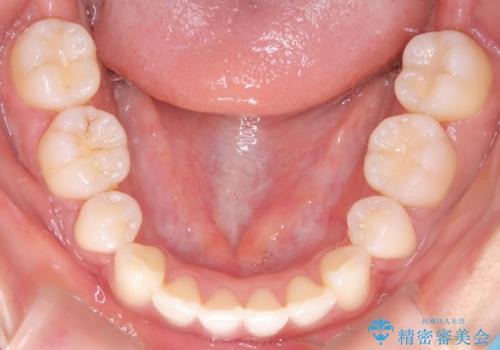

2. 【審美ワイヤー】口元を下げたいの治療中